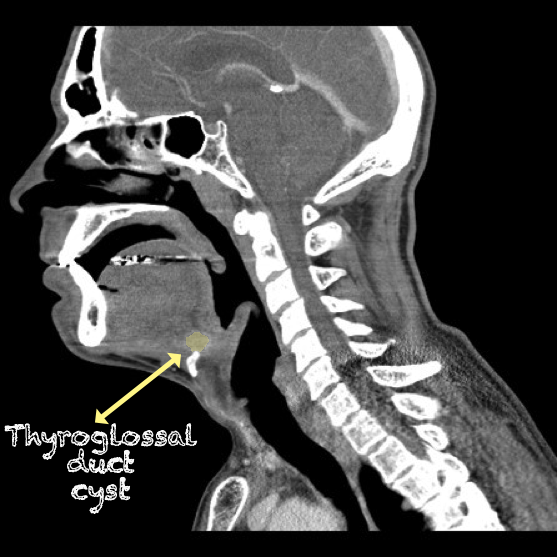

- Thyroglossal Duct Cyst with ring enhancement on CT:

- Figure 36 and 37. Thyroglossal Duct Cyst on CT